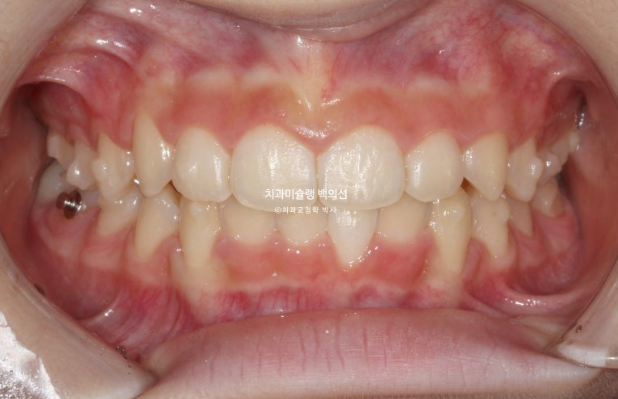

교정치료를 위해 내원한 중학생 친구입니다.

앞니 높낮이 차이가 눈에 띕니다.

가운데 앞니 두개가 내려와 토끼이처럼 보입니다.

윗니가 아랫니를 과하게 덮어 아랫니가 보이지 않을 정도입니다.

과개교합 이라고 합니다.

인비절라인 모더레이트의 적응증인 상태이지만 이 당시에는 모더레이트 포르그램이 런칭 되기 전이였습니다.